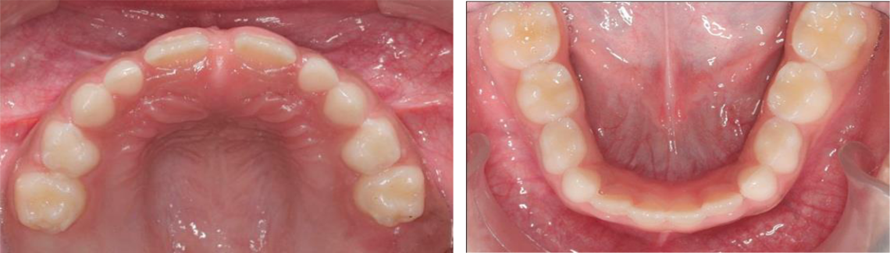

Figura 4. Fotos intrabucales. vista oclusal superior e inferior.

Autor: María Gabriela Flores Bracho. Fuente: Historia Clínica de M. C. M. H. 6 años. 04- 2010

Figura 5. Radiografía panorámica.